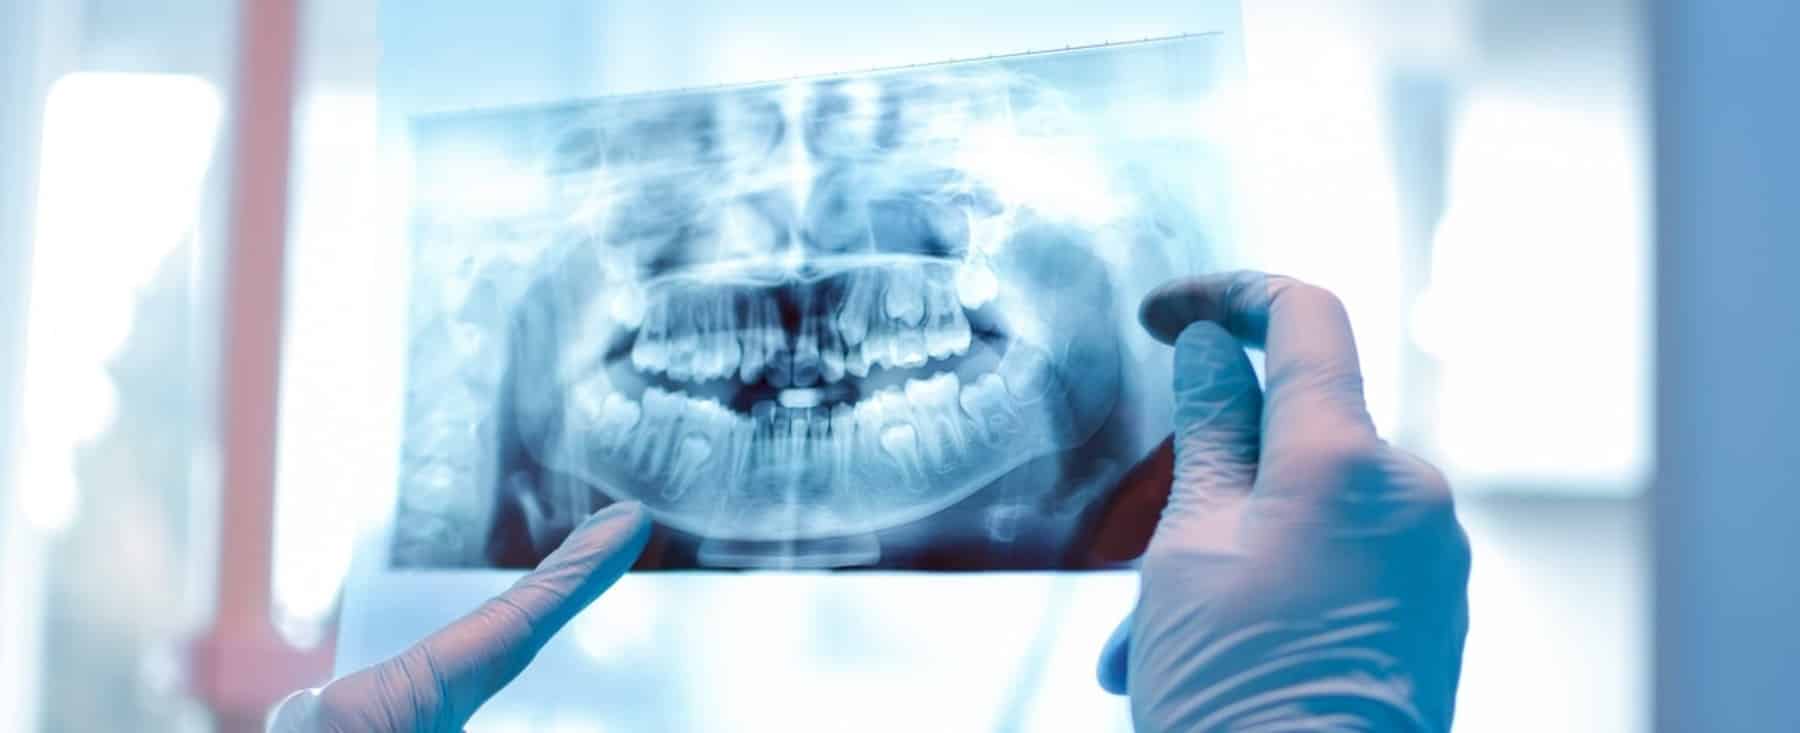

Korrektur von Fehl- bzw. Missbildungen der Kiefer- und Schädelknochen

Kraniofaziale Chirurgie in Berlin Hohenschönhausen

Fehl- bzw. Missbildungen der Kiefer- und Schädelknochen sind in der Regel angeboren und bestehen (wie die relativ häufig auftretende Lippen-Kiefer-Gaumensegel-Spalte) seit Geburt oder entstehen durch falsch verwachsene Schädelnähte. In letzterem Fall sollten regelmäßige Untersuchungen erfolgen, sofern nicht bei Entdeckung der Fehlbildung eine OP erfolgt ist. Die erforderlichen Eingriffe sind so verschieden wie die Fehlbildungsformen. Sollten Sie oder Ihr Kind Anzeichen einer (oder eine bereits diagnostizierte) Fehlbildung aufweisen, helfen wir Ihnen gern weiter.

In unserer Praxis für MKG-Chirurgie in Berlin Hohenschönhausen verfügen wir über umfangreiche Erfahrung in der Diagnostik und Therapie von kraniofazialen Anomalien . Bei uns erwartet Sie eine

präzise Untersuchung und Diagnostik und eine möglichst minimal-invasive und schmerzfreie Therapie.